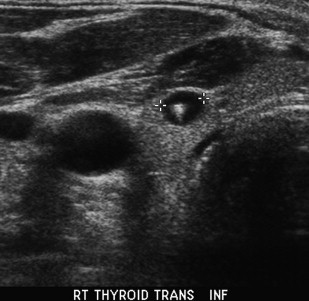

what thyroid pathology is shown here?

colloid cyst